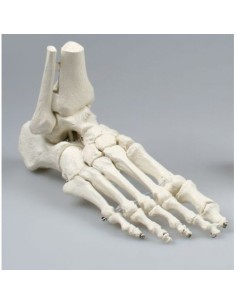

Modèle anatomique du squelette du bassin d'un homme 3B Scientific H21/1

Découvrez le monde de l'anatomie avec des modèles anatomiques de précision

Des modèles anatomiques détaillés pour tous les besoins

Du crâne en 22 parties à verrouillage magnétique aux modèles de colonne vertébrale, des modèles d'articulation aux modèles de cœur, chaque pièce de notre collection est conçue pour une immersion totale dans l'étude de l'anatomie humaine. Nos modèles, réalisés à partir de scans d'os réels, garantissent une expérience tactile authentique et une fidélité de poids presque identique aux originaux.

Indispensables aux étudiants comme aux professionnels, nos modèles anatomiques sont des outils pédagogiques qui permettent d'observer les structures anatomiques avec précision, en évitant les dissections ou les études invasives. Ils sont également utiles pour expliquer les pathologies aux patients, ce qui rend la communication plus efficace et permet de gagner un temps précieux.